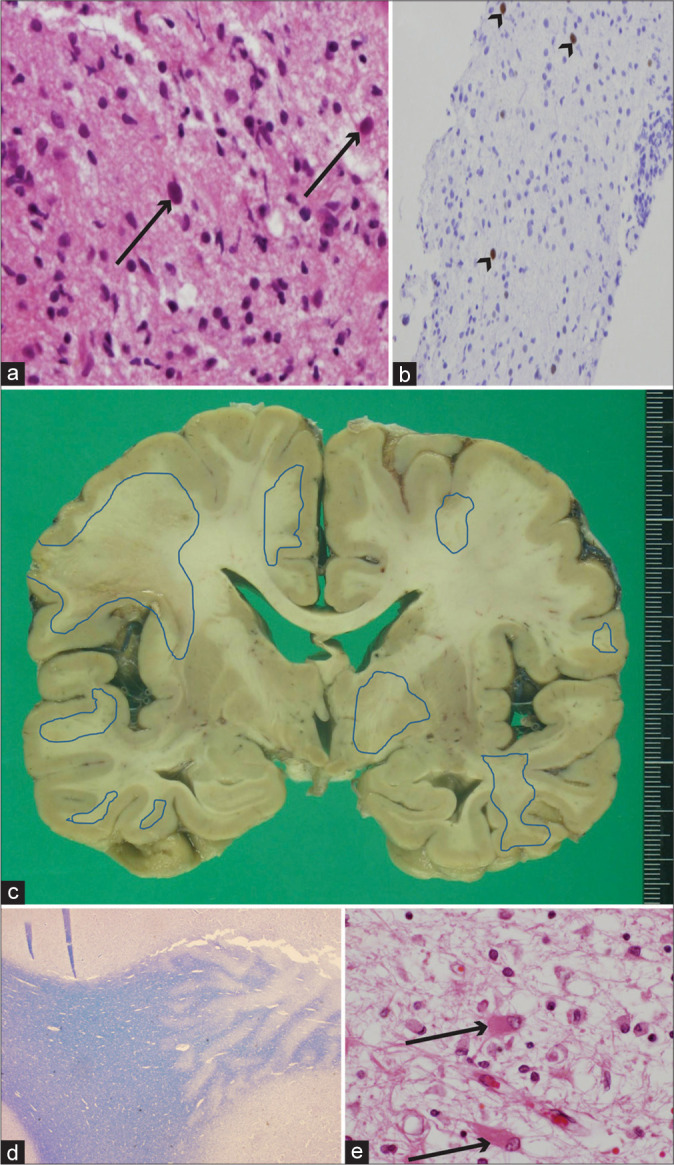

Progressive multifocal leukoencephalopathy associated with rituximab treatment.